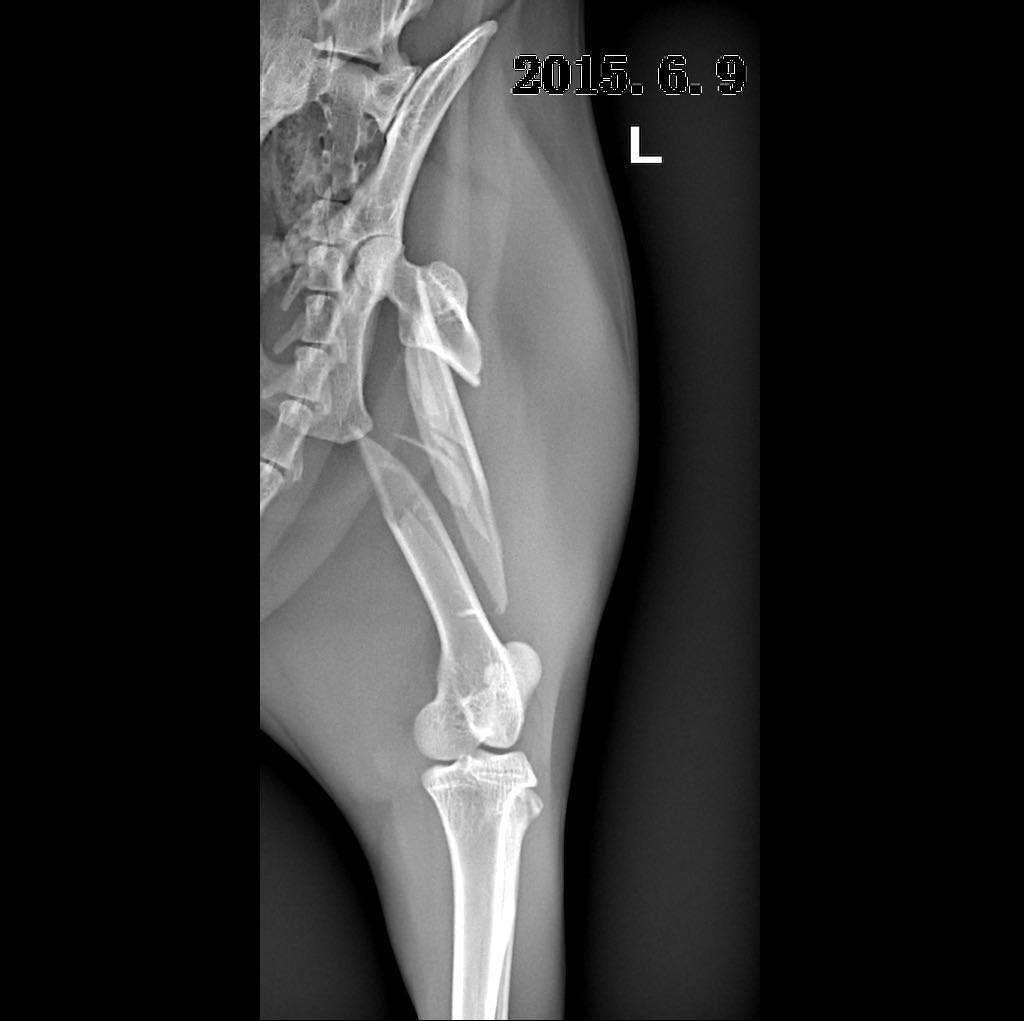

摘 要:动物发生脊椎骨折一般是由大的外力所致:如咬伤、车祸伤或高楼坠伤